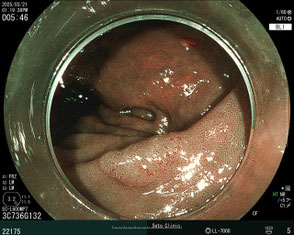

ポリープ治療の事例

通常光でポリープを発見